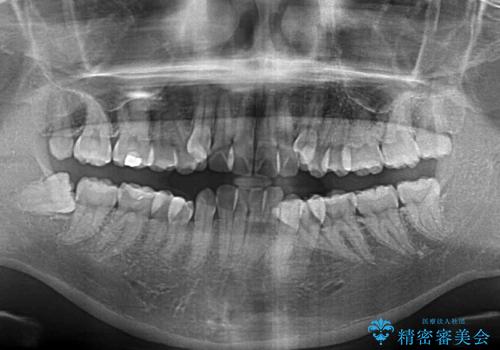

- 治療計画

- 上下の八重歯やデコボコを気にして来院された患者様です。

上下ともに八重歯が顕著であったので、上下左右第一小臼歯4本を抜歯し、補助装置を使用して速やかに改善しながら、ワイヤー装置にて矯正治療を行うこととしました。